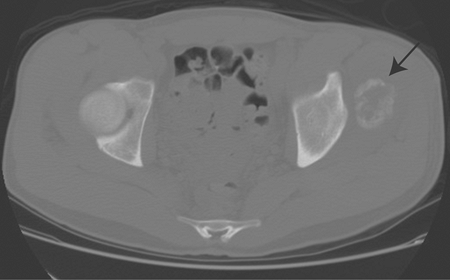

There are four main reasons to obtain a CT scan in patients with soft tissue masses:

-

CT scan of the chest for staging in soft tissue sarcoma

Evaluation of underlying bony involvement (Fig. 2-3)

Evaluation of the primary tumor in patients with contraindication to magnetic resonance imaging (MRI)

Evaluation of pattern of mineralization (Fig. 2-4)

Figure 2-4

Mineralized soft tissue mass in the pelvis. CT scan nicely demonstrates

a zonal pattern of ossification with more mature mineralization

peripherally, consistent with myositis ossificans.-